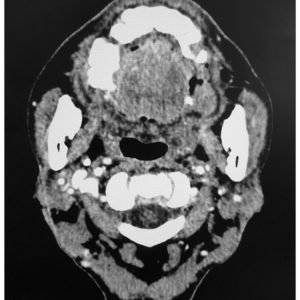

K vòm

Lượt xem: 267» 24-03-2019 -

K vòm

Lượt xem: 268» 24-03-2019 -

K vòm

Lượt xem: 144» 24-03-2019 -

K vòm

Lượt xem: 205» 24-03-2019 -

K vòm

Lượt xem: 162» 24-03-2019 -